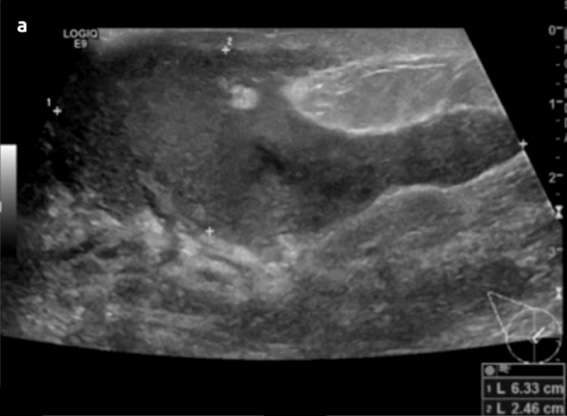

Periductal mastitis is histopathologically defined as a chronic inflammatory condition of the major mammary ducts, with associated duct ectasia and plasma cell infiltration. It is usually seen in reproductive-age women. The cause and pathophysiology is not entirely understood. However, smoking appears to play a role in the development of this condition, either causing direct or indirect damage to the epithelial lining of the milk ducts, leading to inflammation, sloughing of epithelial cells, plugging and dilation of the duct and subsequent infection. Bacteria have also been implicated in the pathophysiology, with isolated organisms including Staphylococcus aureus, Enterococcus, Pseudomonas, Bacteroides, and Proteus species. Clinical symptoms include a subareolar mass with or without associated pain, erythema, nipple discharge, and/or nipple inversion. Imaging features on mammography include characteristic thick, linear, cigar-shaped or rod-like calcifications, with the long axis pointing toward the nipple. These calcifications tend to be longer, thicker, and smoother than calcifications seen with DCIS or ductal carcinoma. Sonographic features typically include dilated intramammary ducts with internal echogenic filling defects and increased surrounding vascularity. Complications are similar to lactational mastitis and include abscess and fistula formation.

Case: Mastitis Figure 2

Figure 2. Images from Leong et al. show imaging features associated with a case of periductal mastitis. Sonographic images show markedly dilated intramammary ducts with intraluminal filling defects and surrounding increased vascularity. Mammogram on the right shows characteristic thick, rod-like and cigar-shaped calcifications with the long axis pointing toward the nipple.